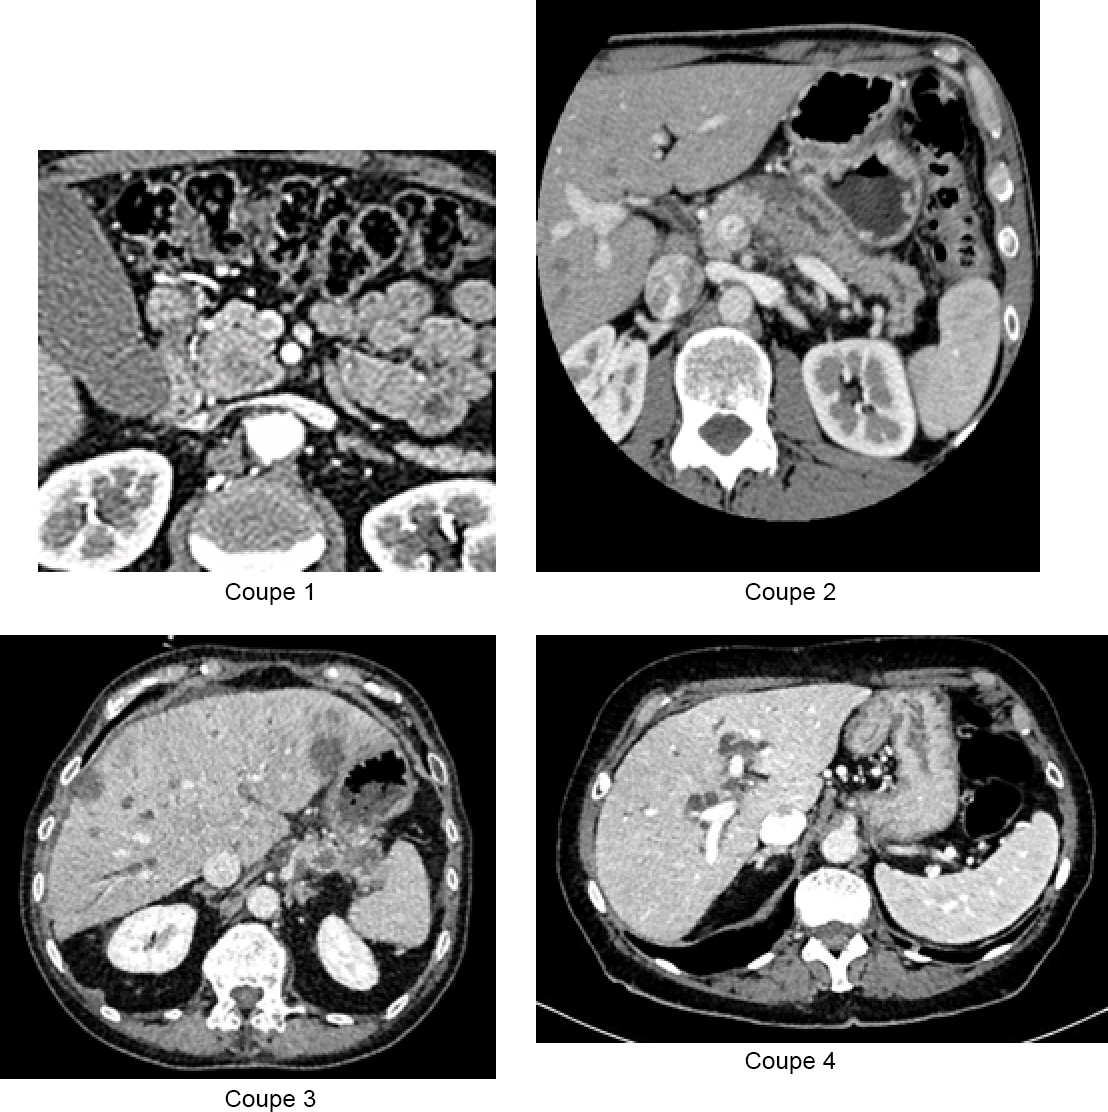

Vous recevez les résultats du bilan biologique : – hémoglobine (Hb) = 10,1 g/dL ; volume globulaire moyen (VGM) = 75 fl ; plaquettes = 550 G/L ; leucocytes = 18 G/L dont polynucléaires neutrophiles (PNN) à 15 G/L ; – natrémie = 136 mmol/L ; kaliémie = 3,4 mmol/L ; créatininémie = 70 umol/L ; – aspartate aminotransférase (ASAT) = 230 U/L (N < 30) ; alanine aminotransférase (ALAT) = 241 U/L (N < 30) ; gamma GT = 879 U/L (N < 60) ; phosphatases alcalines = 967 U/L (N < 100) ; bilirubine totale = 460 µmol/L (N < 17) ; bilirubine conjuguée = 400 µmol/L ; protéine C réactive (CRP) = 300 mg/L ; ferritine = 974 µg/L ; coefficient de saturation de la transferrine = 21 % ; taux de prothrombine (TP) = 45 %, facteur V = 98 %. Voici les coupes de scanner : Figure 1 (Source : Elisabeth Capelle, La Revue du Praticien)

Voir figure 2 dans le commentaire de la question.